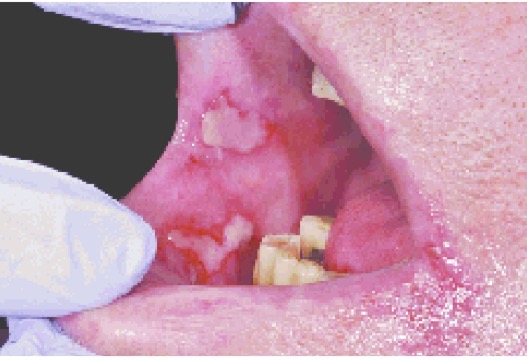

CHẨN ĐOÁN ?

VIÊM NIÊM MẠC MIỆNG DO TIA XẠ